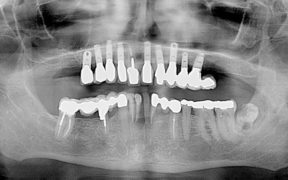

Dr. Bob Wood, specialist in oral and maxillofacial radiology at Princess Margaret Cancer Centre, joins Dr. John O’Keefe in the 7th episode of our video presentation series to help clinicians systematically review and interpret radiographs. Using real clinical cases, Dr. Wood articulates the required steps to get to an accurate interpretation that leads to a precise diagnosis. […]

It is always a pleasure to host Dr. Paul Belzycki on CDA Oasis. He is back with an interesting clinical case and a valuable learning moment. Dr. Belzycki has been in general dentistry practice for forty years and he has shared some of the most viewed presentations here on Oasis. We are thankful for his […]